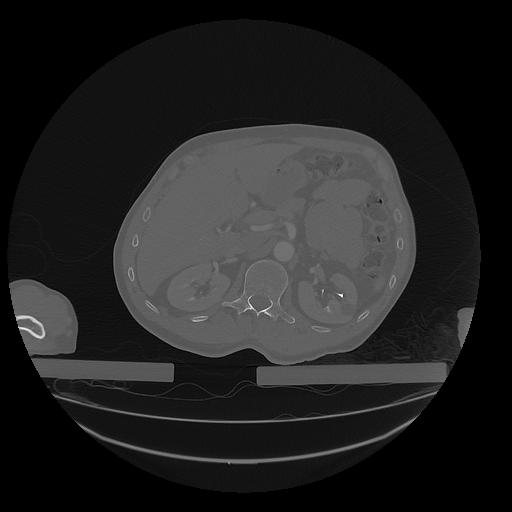

31 PULMON,CE,Vol,1.0,PULMON,,